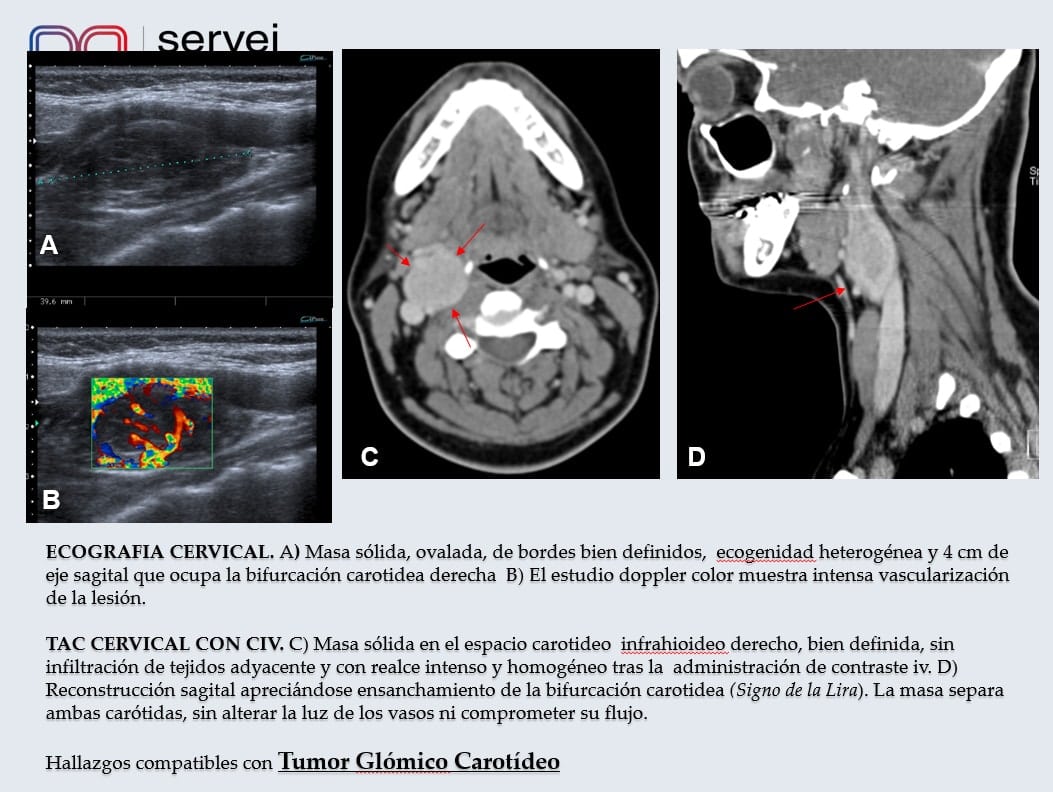

Correlación Histopatológica de Glomus Carotídeo tratado con Onyx y posteriormente resecado